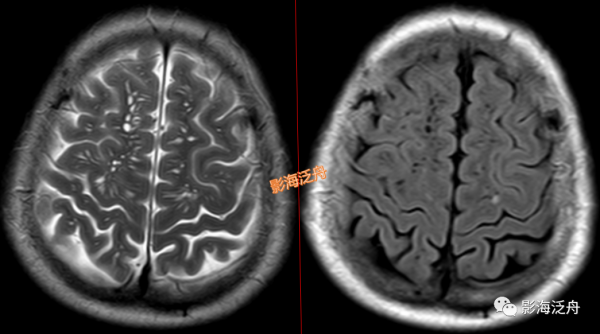

II型-大腦半球型:擴大VR腔隙呈對稱性廣泛分佈於雙側半卵圓中心及皮層下白質區域(黃箭),少位於扣帶回旁(白箭),部分呈類圓形(紅箭頭),部分呈裂隙樣/線樣(藍箭頭),注意綠箭頭所指的VR腔隙邊緣可見Flair高訊號影,這種高訊號可能是區域性液體少量滲漏造成的。